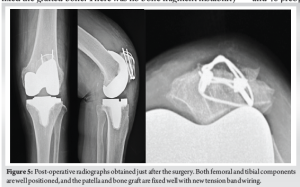

Surgery was performed under general anesthesia with a tourniquet. The previous skin incision was used and extended, and a medial parapatellar arthrotomy was performed. First, the femoral and tibial implants were replaced. An Attune knee system (DePuy Synthes, Warsaw, IN) with a fixed-bearing posterior cruciate-stabilizing prosthesis was used. The surgical epicondylar axis was used as the index for the rotation of the femoral component, and the Akagi line for the rotation of the tibial component. The cartilage of the patellofemoral joint was completely absent. The non-union fracture line was observed on the articular surface of the patella (Fig. 3). Next, surgery for non-union of the patella was performed. We removed the surgical wires of TBW, leaving the straight steel wires in place, and debrided the pseudarthrosis on the anterior surface of the patella using a Surgairtome. The debrided area of the pseudarthrosis was 10 × 20 mm. We transplanted autograft bone obtained from the TKA resection into this defect and performed a new TBW (AI-Wiring System; Aimedec MMT, Tokyo, Japan) (Fig. 4). The surgical wire used in the TBW firmly fixed the grafted bone. There was no bone fragment instability of the treated patellar non-union through 90° of knee flexion, and patellar tracking was acceptable. We decided not to perform patellar replacement because of concerns about bone loss due to OA and instability around the patellar non-union, even after the ORIF with bone grafting. To prevent ischemia of the patella, we also did not perform lateral release or lateral patellar facetectomy [5] (Fig. 5). Postoperatively, full weight-bearing walking was started 1 day after surgery. Knee immobilization with a brace was applied for 1 week. From the 2nd to 3rd week, the range of flexion gradually increased to 90°. After 3 post-operative weeks, the patient was allowed full ROM. At the 1-year follow-up, the patient was able to walk with a cane and the ROM of the left knee was 0–125° (0–120° preoperative). Her left knee pain decreased to 1 (8 preoperative) on the NRS. Patellar bone union was observed without obvious loosening of the implants (Fig. 6), and the KS knee score and function score had improved to 89 and 65 (53 and 40 preoperative), respectively. At the 2-year follow-up, her left knee pain was 0 on the NRS, and the KS knee score and function score were maintained.